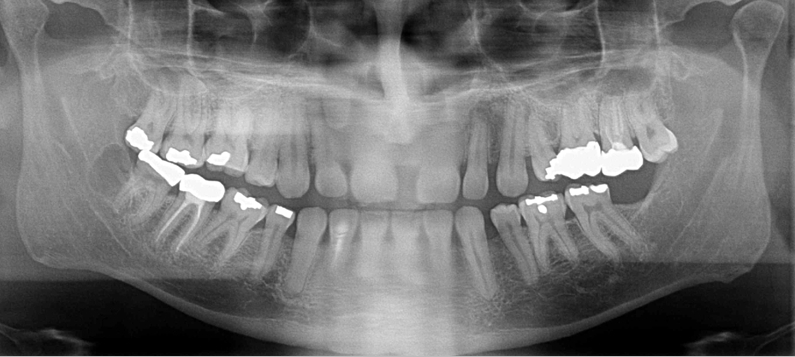

What is wrong with this image?

chin down

rami tipped in; OP very smiley